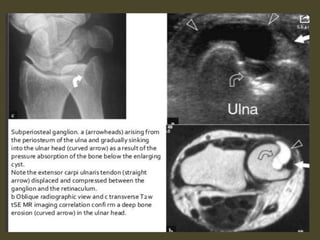

Ganglion cyst.